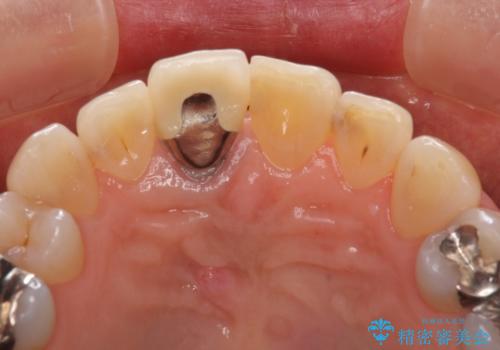

金属を全てセラミックに メタルフリー治療

- 口腔内にある銀歯を全て外したいとのことで来院された患者様です。

土台に含まれている金属も含め、口腔内の金属は全て除去し、抜歯しなければならない歯は抜歯し、オールセラミッククラウンやセラミックインレーにて治療することとしました。